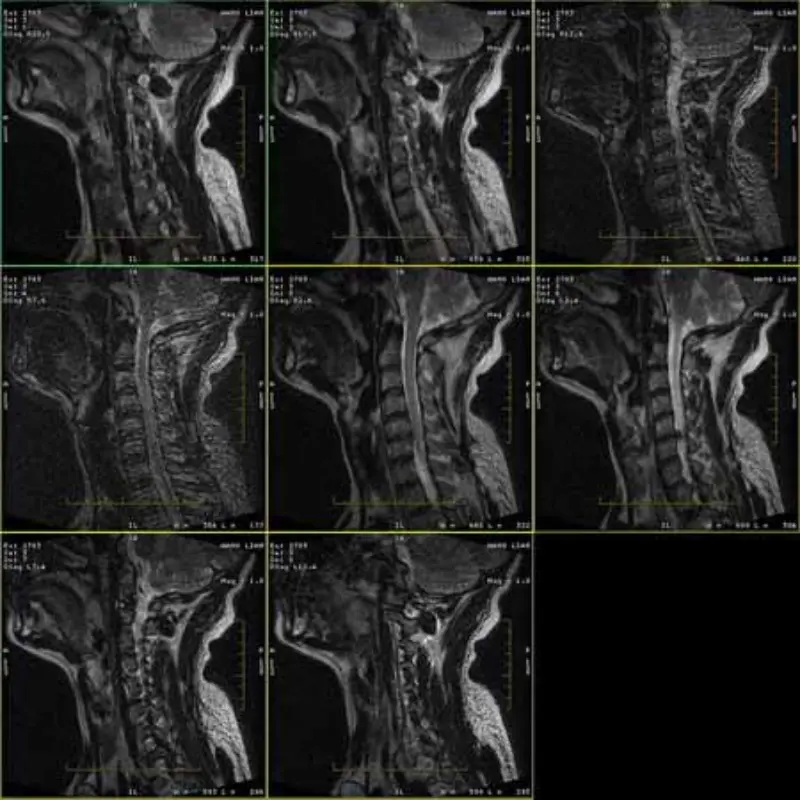

FRFSE మరియు GRE ప్రోటోకాల్‌ల ఇమేజ్‌లు దెయ్యాన్ని కలిగి ఉంటాయి మరియు కొన్నిసార్లు తక్కువ SNR చిత్రాలు ఒక సిరీస్‌లో కనిపిస్తాయి. కానీ SE ప్రోటోకాల్ చిత్రాలు సాధారణమైనవి.

దయచేసి అటాచ్ చిత్రాలను చూడండి.